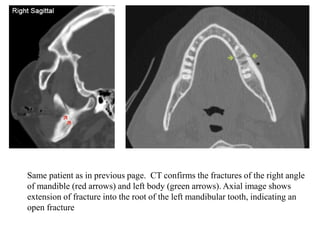

43-year-old man, fell from height, presented with

malocclusion Orthopantogram demonstrates a fracture of the

right ramus of mandible (red arrows). Subtle ‘second’ site of

fracture is at the left body (green arrows) which is confirmed

in CT scan

Same patient as in previous page. CT confirms the fractures of the right angle

of mandible (red arrows) and left body (green arrows). Axial image shows

extension of fracture into the root of the left mandibular tooth, indicating an

open fracture